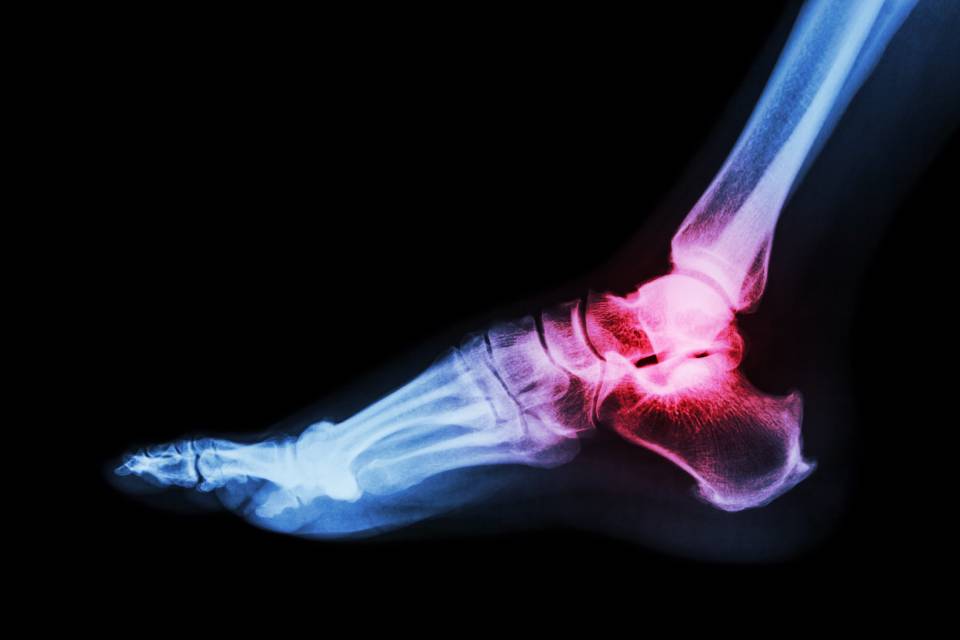

Il Dr. Mocci Andrea è un ortopedico della caviglia a Bari di grande esperienza, specializzato nella chirurgia del piede e della caviglia. Presso Anthea Hospital, struttura moderna e attrezzata con tecnologie avanzate, il Dr. Mocci offre trattamenti personalizzati e all’avanguardia per una vasta gamma di patologie articolari. Il suo approccio è caratterizzato da una particolare attenzione alla qualità della vita del paziente, con interventi mininvasivi che permettono una rapida ripresa e riducono al minimo i tempi di recupero. Grazie a una solida esperienza e un continuo aggiornamento professionale, il Dr. Mocci è in grado di affrontare anche i casi più complessi, garantendo risultati eccellenti.

Nel campo della chirurgia della caviglia, il Dr. Mocci Andrea offre una vasta gamma di interventi per trattare le patologie più comuni e complesse. Tra i trattamenti che esegue ci sono:

- Artroscopie, artrodesi e protesi di caviglia, particolarmente utili nei casi di artrosi grave o lesioni articolari avanzate;

- Traumatologia della caviglia, che include la gestione delle fratture e distorsioni;